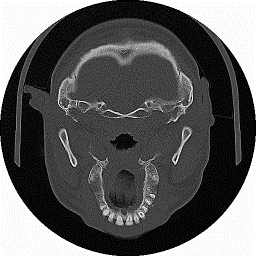

Figura 1‑2 Immagine TAC relativa ad una sezione trasversale del cranio.